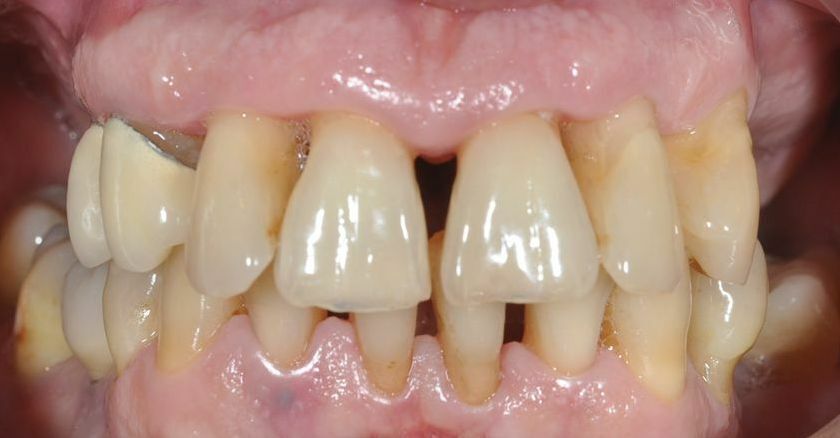

AVANT

Une préparation parodontale s’avère nécessaire pour permettre l’orthodontie.

Le cliché panoramique initial montre de nombreuses infections dentaires et un polype dans le sinus maxillaire gauche. Une première prothèse amovible venait remplacer deux molaires au maxillaire gauche et une seconde une prémolaire et deux molaires à la mandibule droite.